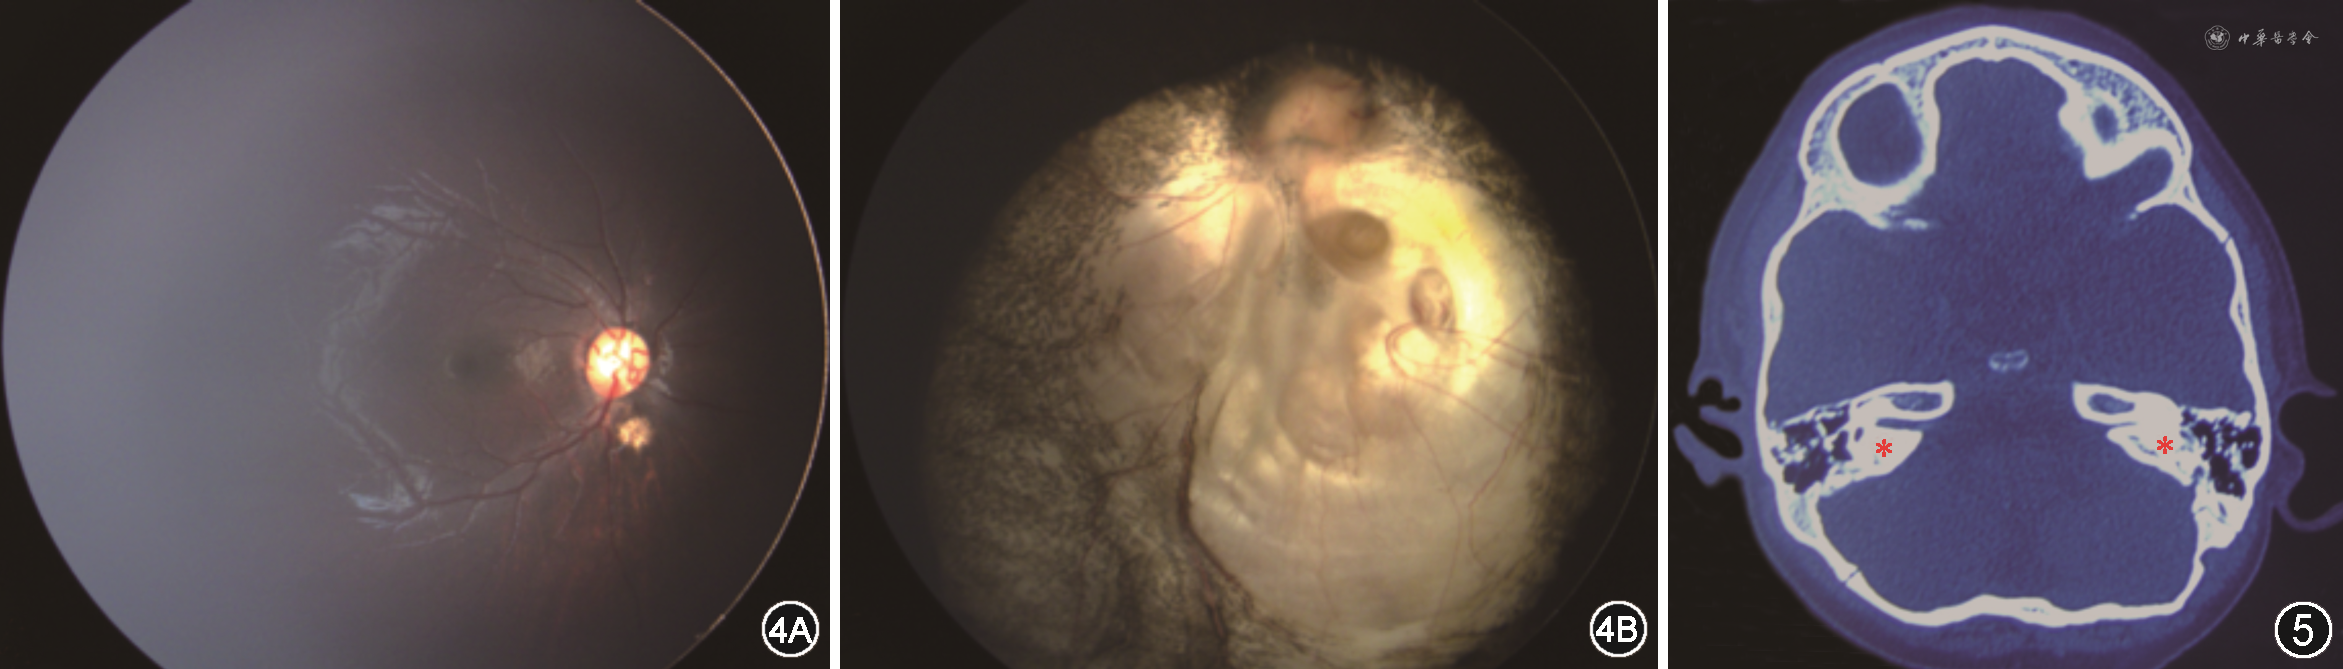

查体:患儿精神一般,行走不稳;面部不对称,左侧鼻唇沟变浅,额纹消失,口角向右侧偏斜(图1);右耳廓形态畸形,左耳廓结构畸形,部分缺损(图2,3),双侧外耳道未见明显异常;心前区未闻及病理性杂音。眼科检查:视力:条栅无明显注视行为,视动性眼震仪双眼阳性,单眼遮盖拒绝;眼位:33 cm映光交替遮盖:正位至+15°,偶有L/R 5°;遮盖去遮盖检查不配合;双眼各方位运动无明显受限,左眼睑闭合欠佳,双眼结膜无充血,角膜透明,瞳孔圆,直径约2.5 mm,直接、间接对光反射灵敏,晶状体透明。广角数码儿童视网膜成像系统(RetCam3,美国Clarity公司)眼底检查:右眼视盘边界清,色淡红,视网膜平伏,血管走行可,视盘下方见1/4 视盘直径大小脉络膜缺损灶(图4A);左眼视网膜平伏,下方大片状脉络膜缺损灶累及视盘及黄斑区(图4B)。1%阿托品散大瞳孔验光:右眼+1.75 DS(矫正不理解),左眼-9.00 DS(矫正不理解)。眼部B超:眼轴长右眼20.8 mm,左眼24 mm,左眼球后壁不光滑,双眼未见视网膜脱离光带。纤维鼻咽喉镜检查:双侧腺样体稍大,双侧扁桃体大,鼻部发育无异常。颞骨CT检查:左侧听小骨发育不良,左侧蜗神经闭塞,左侧内听道狭窄,右侧蜗神经孔稍窄,双侧半规管显示不良,提示发育不全(图5)。听力检查提示双耳感音神经性耳聋(左耳极重度)。心脏彩色超声检查:动脉导管结扎术后,血流正常。泌尿生殖系统B超检查未见明显异常。外周血行NGS基因检测结果显示:患儿CHD7基因发现c.3392T>C(编码区第3392号核苷酸由T变为C)的杂合核苷酸变异,该变异导致1131号氨基酸由亮氨酸(Leu)变为脯氨酸(Pro)。

结合患儿病史、临床表现及辅助检查诊断为:CHARGE综合征(双眼先天性脉络膜缺损、左眼睑闭合不全、左眼知觉性内斜视、双眼屈光参差、左侧面神经麻痹、先天性耳廓畸形、感音神经性耳聋、运动发育迟缓、精神发育迟缓、心脏动脉导管结扎术后)。